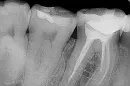

Ниже прилагаю фото этого зуба после последнего перелечивания. Также прилагаю рентгеновский снимок (семерка, о которой идет речь, живая, рядом мертвая шестерка). Зуб был перелечен 12.09.2014г.

Я рассказал о болях стоматологу. Зуб был перелечен стоматологом с удалением старой пломбы и покрытием всей жевательной поверхности зуба одной монопломбой. На фото как раз результат этого перелечивания. Зуб опять перелечивался на стоматологическом лазере. Травление не производилось, полость после обработки (которое эквивалентно высверливанию убираемых тканей) была обработана специальным режимом лазера для лучшей адгезии (сцепления). Двумя присутствовавшими врачами (именно врачами, а не врачом и медсестрой) полость после «высверливания» была диагностирована как средний кариес.